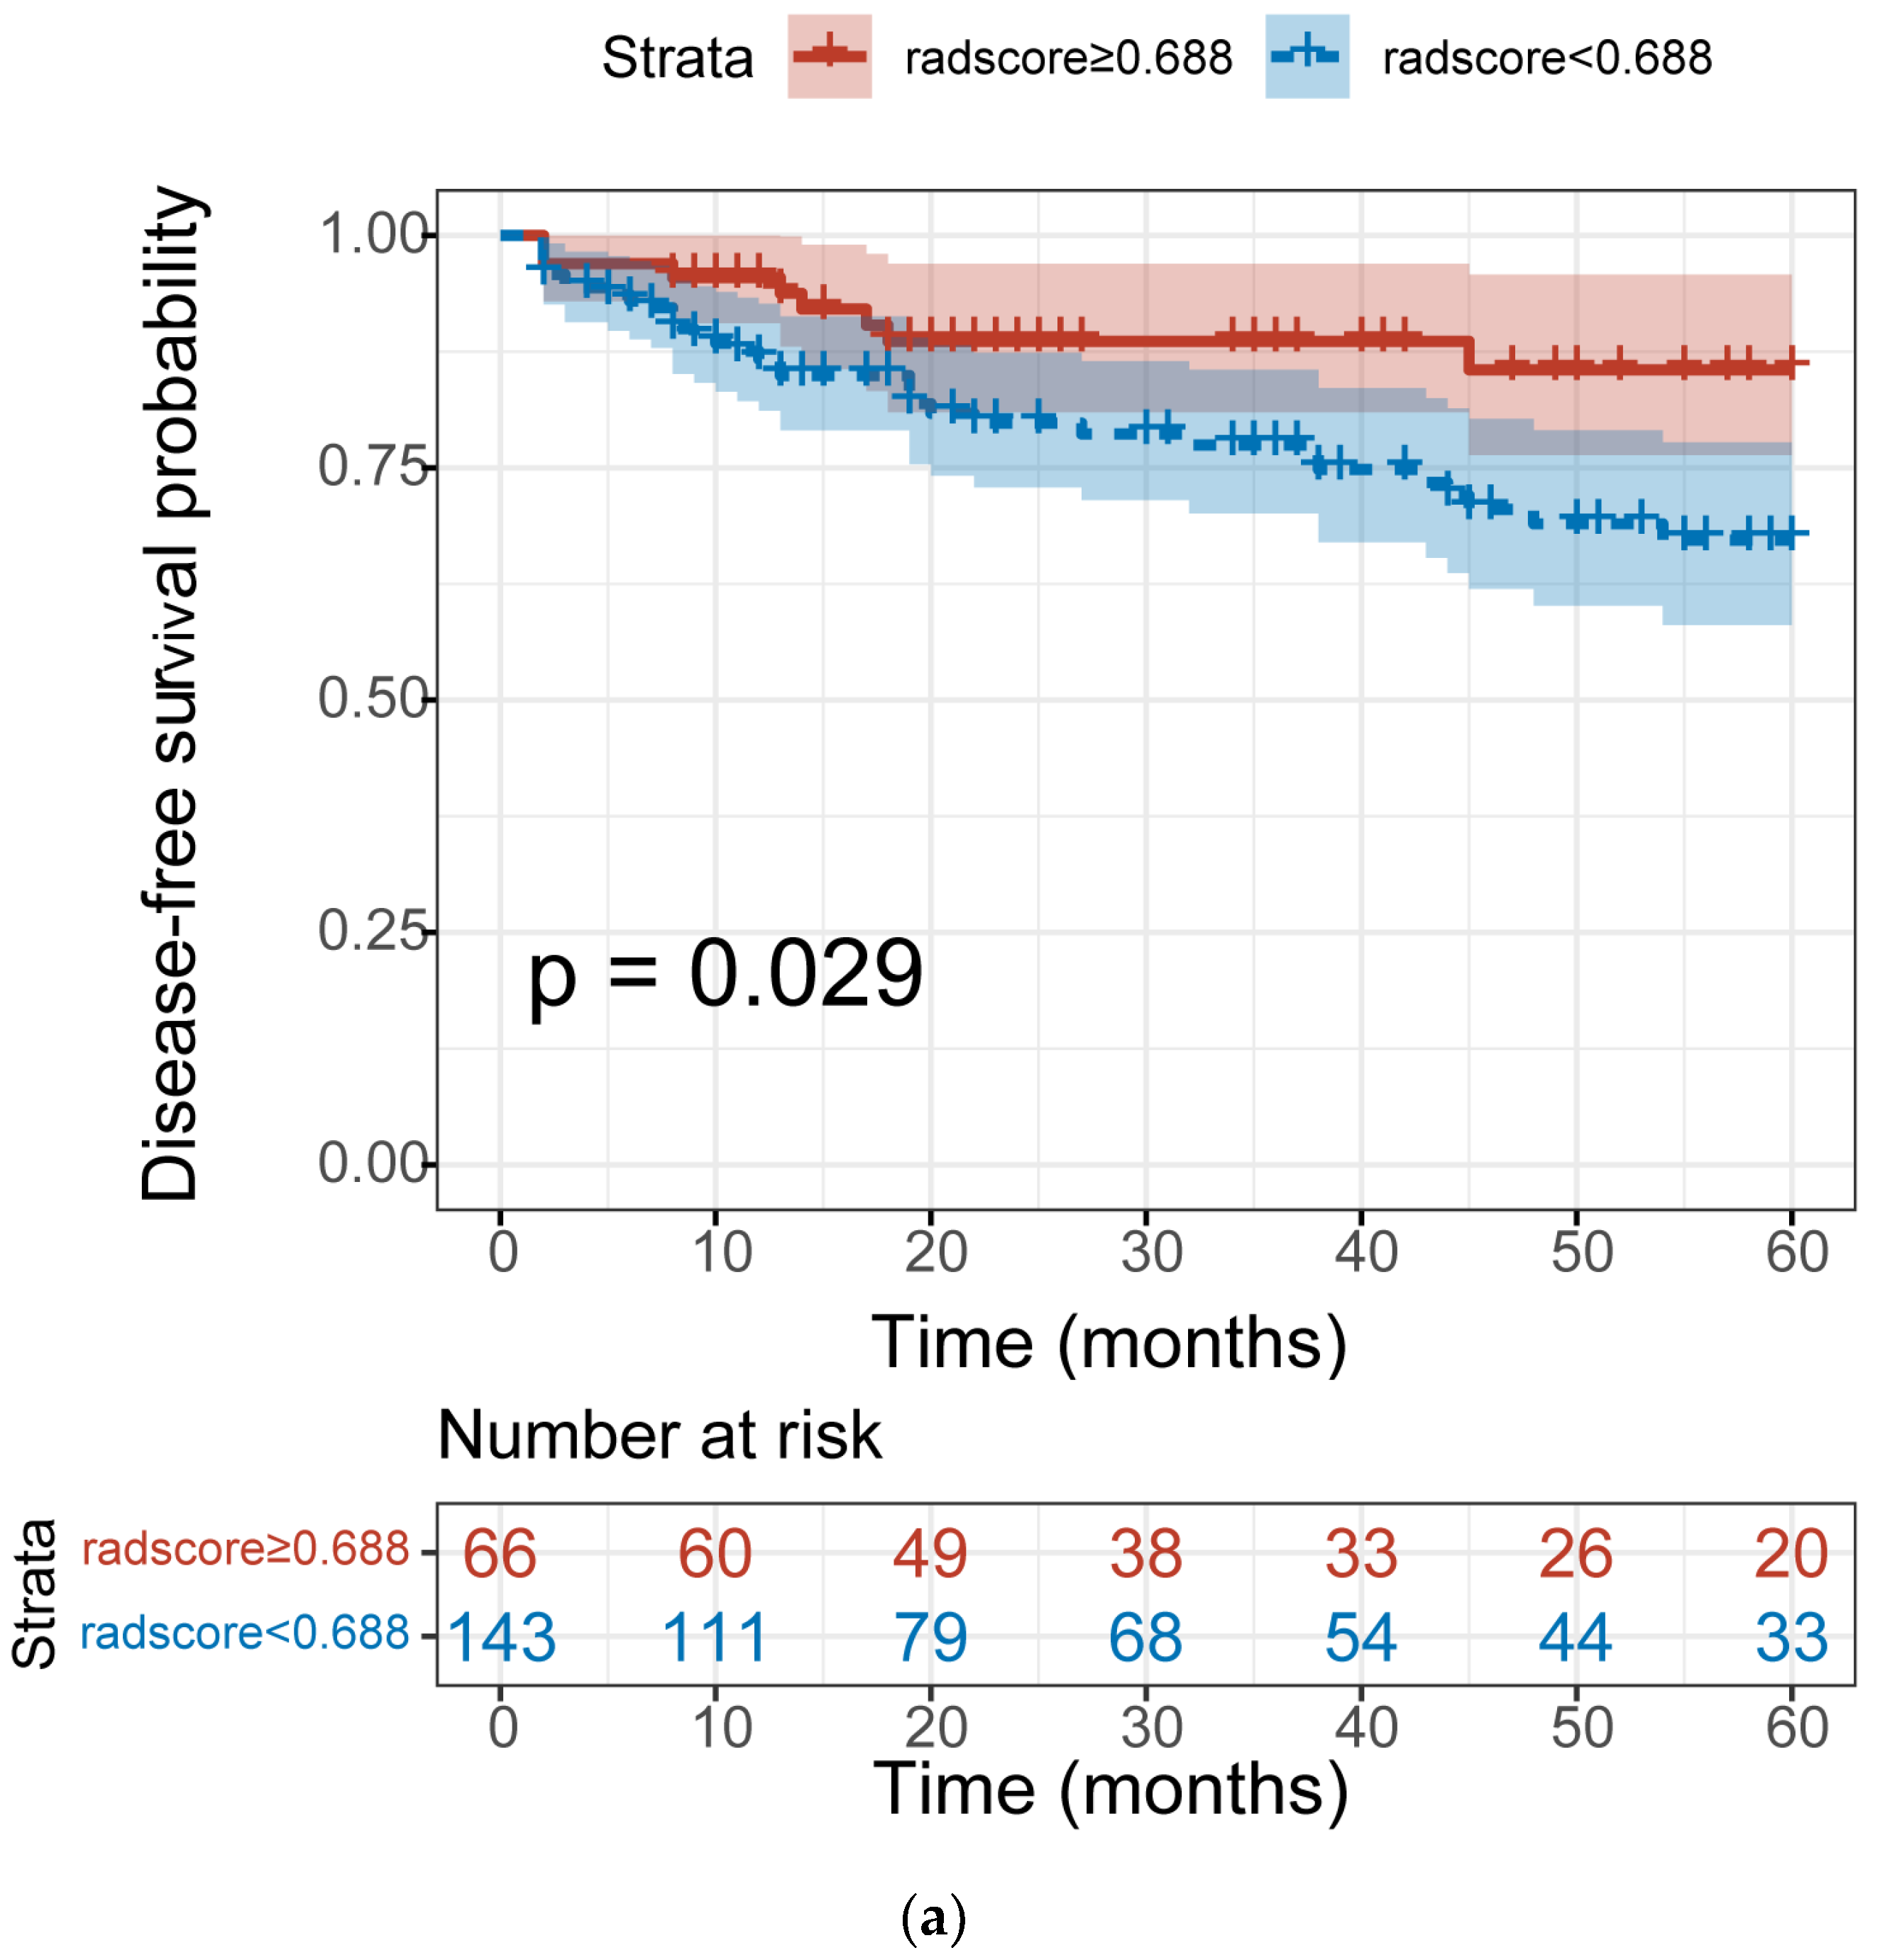

3.5. The Association between Radscore and Disease–Free Survival

| radscore | 0.034 | 0.576 | 0.78 | |||

| ≥0.688 | 52 | 1 | ||||

| <0.688 | 157 | 2.303 (1.065–4.977) | 1.126 (0.489–2.595) | |||